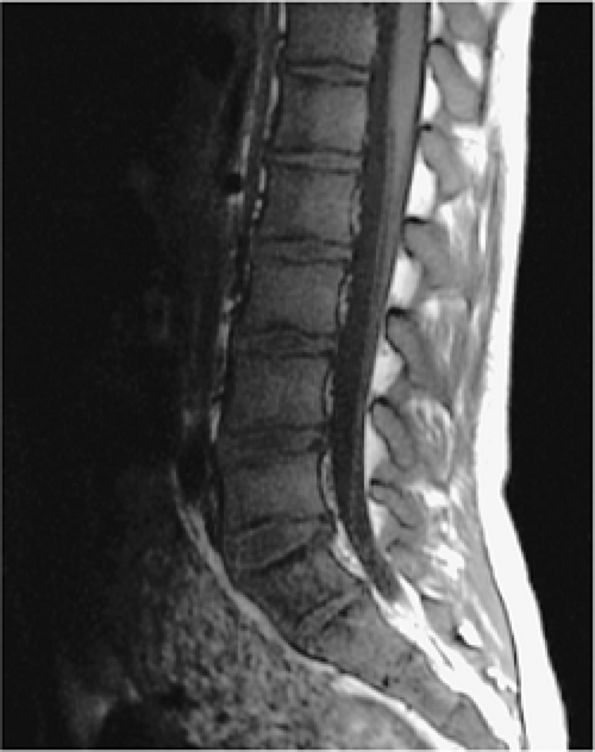

FIGURE 13.88 ● Yellow to red marrow conversion in a patient with thalassemia shows low-signal-intensity hematopoietic marrow on a sagittal T1-weighted image.

|